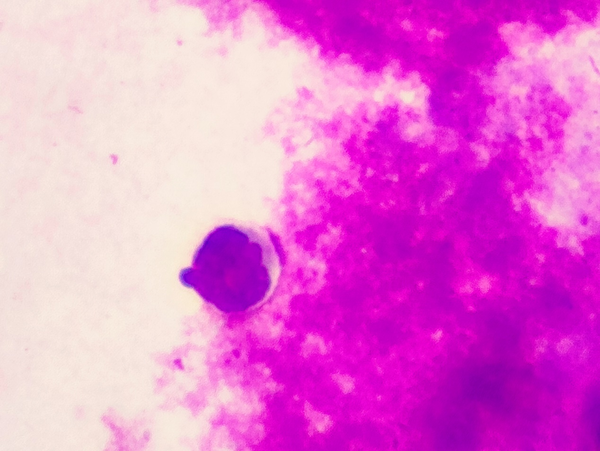

孙利娜在与眼底病专家李玉军、检验科等多科室会诊后,决定抽取赵女士眼内房水及玻璃体标本做相关检测,确定病源。而稍后的检测结果却令人不寒而栗。

赵女士眼内竟然存在玻璃体视网膜淋巴瘤(vitreoretinal lymphoma,VRL)。

▲赵女士检验报告

然而,通过详细的眼部B超、OCT(光学相干断层扫描)检查,尤其是关键的诊断性玻璃体切割手术及病理检测,最终在眼内玻璃体液中发现了恶性淋巴瘤细胞。